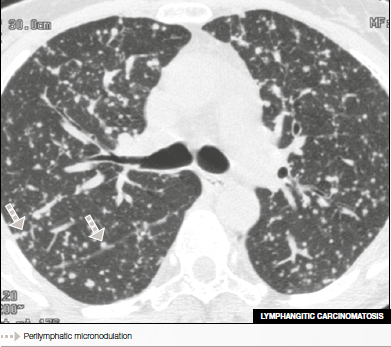

Patient presenting an adenocarcinoma in the stomach and micronodulation of the lung with a perilymphatic distribution related to lymphangitic carcinomatosis.